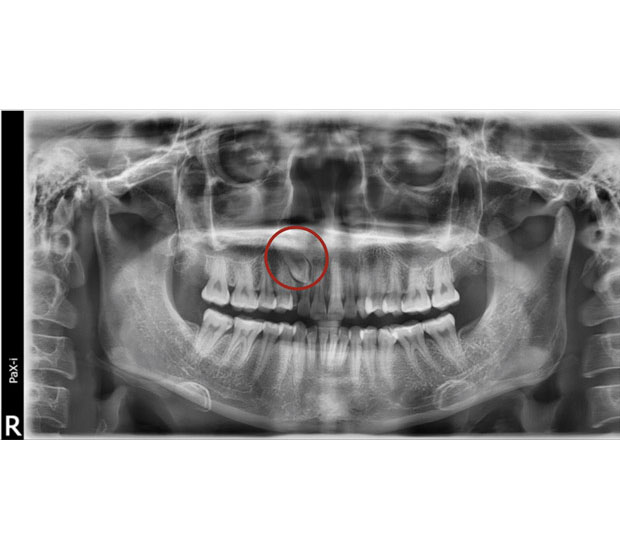

Assessment: First, your orthodontist and oral surgeon will evaluate your dental situation, usually with the help of X-rays or 3D imaging. They will determine the best course of action to help the impacted tooth move into the correct position.

Surgical Exposure: If it's necessary, the oral surgeon will perform a surgical procedure to expose the impacted tooth. This involves making a small incision in the gum tissue to access the tooth beneath.

Obstacle Removal: Sometimes, there may be obstructions like dense bone or other teeth that are in the way of the impacted tooth. The oral surgeon can remove these obstacles during the procedure.